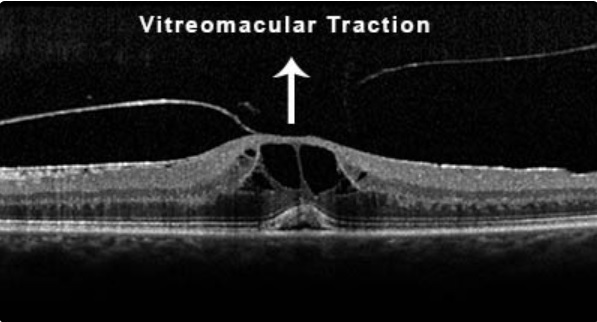

O que é a Síndrome de Tração Vítreomacular?

- DVP parcial, com forte adesão na região macular, associada a tração nesta região, distorcendo a arquitetura local.

Qual é o quadro clínico apresentando pelos pacientes com STVM?

Edema Cistóide

Descolamento da fóvea

Buracos lamelares

Qual é a classificação da STVM?

Adesão Vítreomacular: sem distorção da arquitetura macular

STVM Focal: adesão menor 1500 micrômetros

STVM Difusa: adesão maior 1500 micrômetros